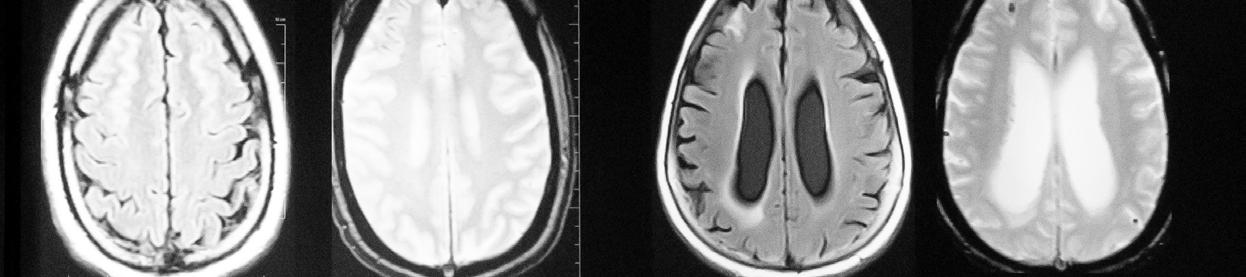

Conventional MRI scanners for clinical use generate images using magnets whose strength is measured at 1.5 Tesla (T) or 3T. At a limited number of locations across the world, clinicians and researchers have access to MRI scanners with much more powerful magnets operating at 7T. With the several dozen 7T machines located in the United States, imaging scientists can gain much higher resolution images, examining the tiny details that make up the architecture of the brain and body. However, there is still a ceiling to that resolution, as even with the most optimal scan parameters, features smaller than one to two millimeters vanish into the abstraction of the voxel, a three-dimensional pixel.

In December 2023, an international team of scientists including UCSF faculty member An (Joseph) Vu, PhD, broke that ceiling. Led by UC Berkeley professor and president of Advanced MRI Technologies, David Feinberg, PhD, MD, the team is a multi-institution collaboration with scientists from UCSF including Drs. An (Joseph) Vu and Pratik Mukherjee, UC Berkeley, Harvard, Siemens Healthineers (Erlangen, Germany), Advanced MRI Technologies (Sebastopol, CA), and MR CoilTech LTD (Glasgow, UK). Together, they constructed a next generation ultra-high resolution 7T MRI scanner, which achieves up to 10-fold increase in resolution over the current 7T standard, which is 50 times more detail than the hospital standard 3T scanners. With this new tool, functional images can now be captured with a voxel size of less than half a millimeter. This allows scientists to, for the first time, image functional clusters of neurons across

the entire brain, organized in cortical cell layers and cortical columns, opening up the study of a new realm of meso-scale local neurocircuitry.

Thanks to additional funding obtained by Drs. Vu, Feinberg, and Alexander Beckett, the NexGen 7T is now available to scientists across the Weill Neurohub consortium of UCSF, UC Berkeley, and the University of Washington, and as an international resource through the NIH BRAIN Initiative. The NexGen 7T MRI scanner is described in a Nature Methods article “Next-generation MRI scanner designed for ultra-high-resolution human brain imaging at 7 Tesla.”1

Although the NexGen 7T is not yet FDA approved, it has achieved remarkable breakthroughs in fast, high-resolution neuroimaging by virtue of several key advancements: an extremely powerful head gradient system, the first 128 channel receiver systems integrated into a 7T scanner, and several universally optimized RF pulse sequence protocol.

NexGen 7T 0.6 mm isotropic diffusion images (b=0 s/mm2) depicting fine anatomical structures including hippocampal layers and perivascular spaces.

Another breakthrough came via the development of 64 channel and 96 channel receiver arrays coupled with the 128-channel receiver system, vastly improving on the standard 32 channel system in terms of SNR and the ability to accelerete the imaging. As the number of receiver channels increases, the size of the individual coil loops in the head coils become smaller, which in turn provides higher sensitivity and improved ability to accelerate data acquisition for fast, ultra-high resolution functional and structural MRI.

The improvements are not only related to hardware, as RF pulse sequence design has played a great role in these milestone achievements. In collaboration with Dr. Nicolas Boulant (CEA, NeuroSpin, France), the team has implemented precisely pre-calibrated universal pulses which can produce structural images of exquisite quality on almost any subject you place inside the scanner without the need for lengthy pre-scans or subject-specific calibrations. Furthermore, in two collaborations with Dr. Renzo Huber (NIMH, NIH) and with Dr. Suhyung Park (Chonnam National University, S. Korea), improvements in functional imaging pulse sequences more precisely identify neuronal activity in cortical layers, and similar resolution gains in collaboration by achieving unprecedented isotropic resolution in the 0.35mm – 0.6mm range.

Feinberg points out, “The NexGen 7T scanner achieves greatly improved precision in diffusion imaging of axonal fiber tracks from the cumulative gains of high signal from 7T and the much stronger gradient encoding, now possible. Secondly, the scanner’s ability to achieve

mesoscale functional imaging at depths in the cortex rather than averaging across the cortex provides more precise information to take new directions in neurocircuitry studies of different neurological disorders including depression, chronic pain, localization in epilepsy and revealing the underpinnings of many cognitive disorders.”

Vu is excited about the new avenues this next-gen 7T scanner will open up, explaining that “Traditionally, the RF pulse sequence optimization is a very involved process done on a per subject basis. One had to acquire calibration scans, model the head, and calculate how best to excite the whole brain. Not every 7T site has the time, expertise, and capability for such an optimized scan protocol. However, with the new universal pulses pre-calibrated technique the images come out very nice on any subject, right out of the box. In the past, some clinicians and collaborators have been hesitant to go to 7T because such technology was not readily available. But with these new NexGen 7T technologies, it removes the hesitancy bottleneck for wide-spread adoption into clinical neuroimaging and research. It is a game changer!”

NexGen 7T 0.9 mm isotropic diffusion tensor images showing impressive anatomical quality and detail throughout the brain.